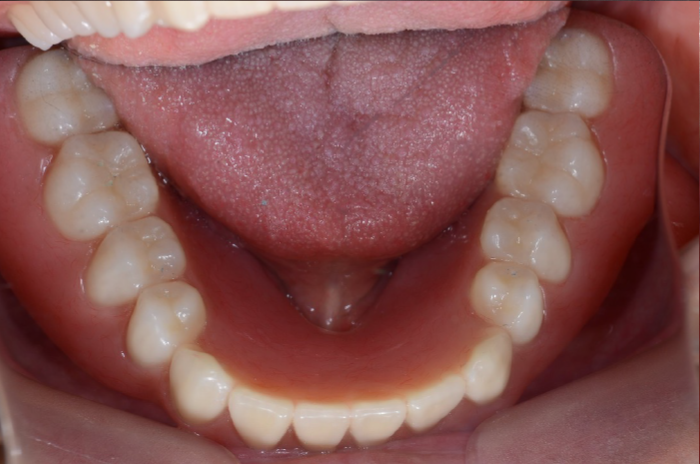

治療用義歯装着

1年6ヶ月後の口腔内